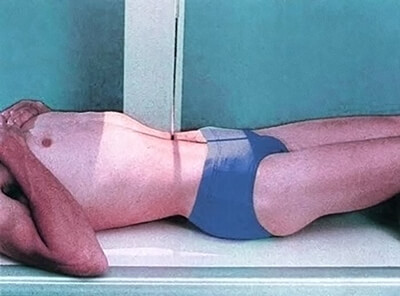

AP Decubitus Abdominal X-Ray

Now, for the AP Decubitus Abdominal X-ray, as shown here, the patient is in supine lying on his left side with knees slightly flexed and arms overhead at 48in from the X-ray tube. The midsagittal plane of the body shall be centered to the midline of the image receptor.

Center the central ray to the midsagittal plane at the level of the iliac crest and shield appropriately with gonadal shielding over the testes in males. Again no shielding is applied for female patients as it will directly obscure the anatomy.

Finally, ask the patient to suspend respiration after exhaling to avoid abdominal compression.

- The elevated lateral abdominal wall is included on the image to detect any free intraperitoneal gas

- There should be no blurring of the bowel gas due to respiratory motion

- Soft tissue grey tones demonstrating lateral abdominal wall if possible, psoas muscles, inferior ribs, diaphragm, transverse process of lumbar vertebrae, and superior ilia

- And finally, the anatomy should not be obscured by shielding or marker placement